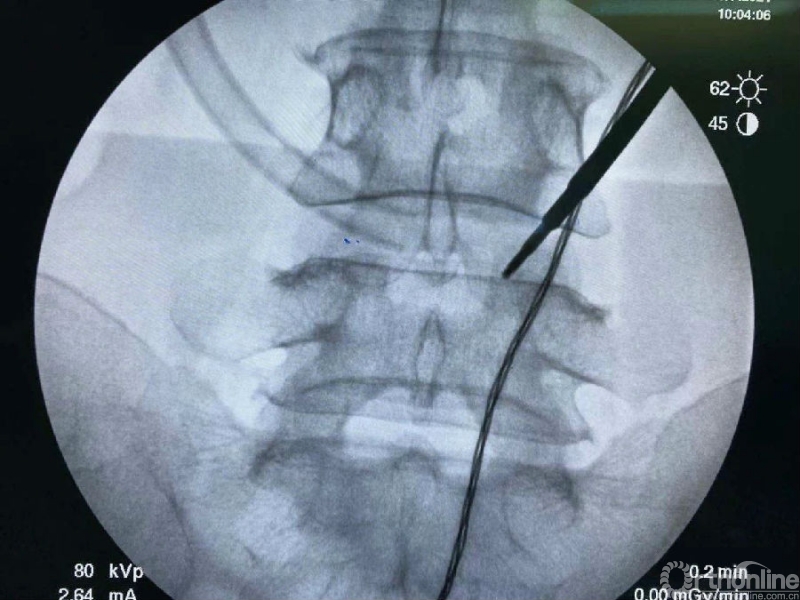

使用磨钻按照范围将下关节突内缘磨薄,然后用骨凿切除下关节突内缘显露出上关节突内缘及关节面。

术中切除下关节突内缘的范围